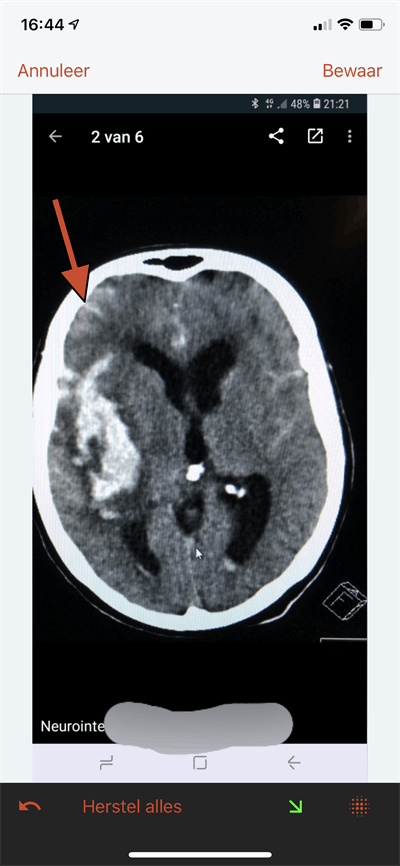

"One of the main reasons is there is a need for fast communication. It is an easy way to efficiently share medical data," noted Ranschaert, adding that a resident might want to get a second opinion on a scan from an interventional radiologist, and if the patient is in a life-threatening situation, every second counts.

However, it is now important to consider the European Union's General Data Protection Regulation (GDPR). When radiologists share images, they must secure the explicit consent of the patient. Moreover, Snapchat or WhatsApp don't allow audit or access control to images, and there is no guarantee the data can be permanently deleted, he explained.

As for sharing those images, Ranschaert wants to educate radiologists and researchers about secure alternatives to public social media software, such as WhatsApp. More secure apps include TigerConnect, Forward Health, Siilo, and Medic Bleep. These are GDPR-compliant, allowing encryption, data transparency, access control, audit control, and anonymity, with formal arrangements for processing and storage, he said. Images taken with a dedicated messaging app, such as Siilo, can be securely stored on remote data servers with strict controlled access to authorized users. Even if the smartphone is stolen, the data can remain safe.